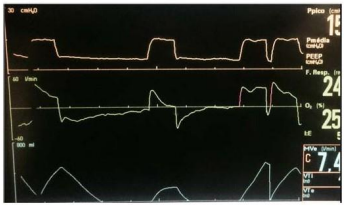

Uma paciente de 58 anos de idade encontra-se mantido em ventilação mecânica invasiva. As curvas do ventilador são as demonstradas na imagem apresentada.

Uma paciente de 58 anos de idade encontra-se mantido em ventilação mecânica invasiva. As curvas do ventilador são as demonstradas na imagem apresentada.